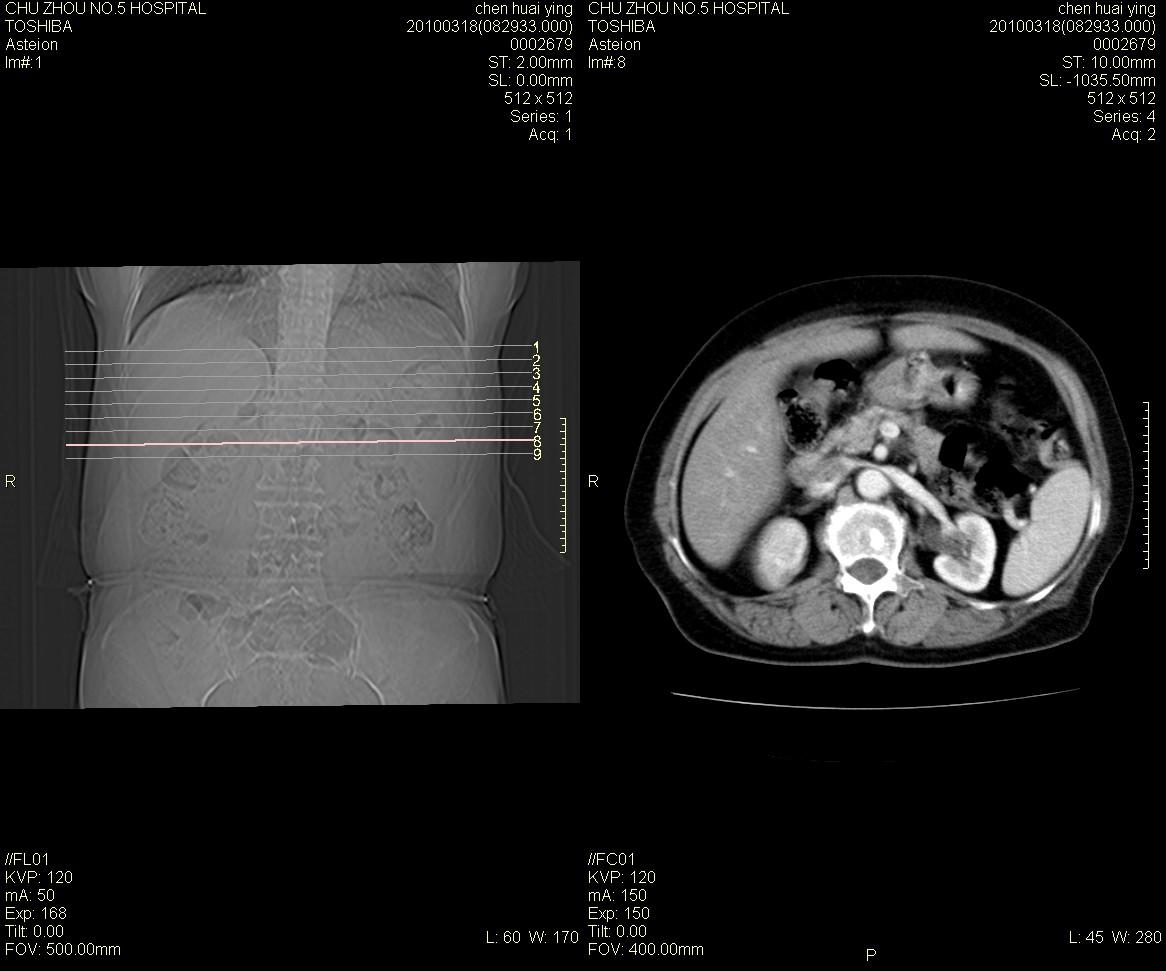

标题: CT25148 肾上腺增强

ct25148增强图片

动脉期太早了,扫的有点低。考虑良性占位右侧肾上腺嗜铬细胞瘤并坏死囊变可能性大,神经鞘瘤不排除。

右侧肾上腺嗜铬细胞瘤并坏死囊变可能性大

考虑双侧肾上腺肿瘤性病变。